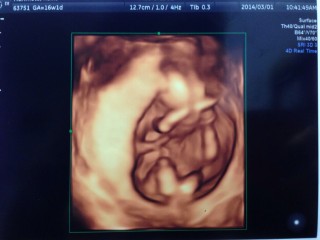

初めて4D撮影をしてもらいました(^-^*)しっかりと体育座りポーズで寝てるよう。現在は体重100グラム位とのこと(^-^)

最初は丸まってて頭からお尻までの大きさを正確にはかれませんでした(-_-;)頭の大きさは3.5センチくらいでした☆